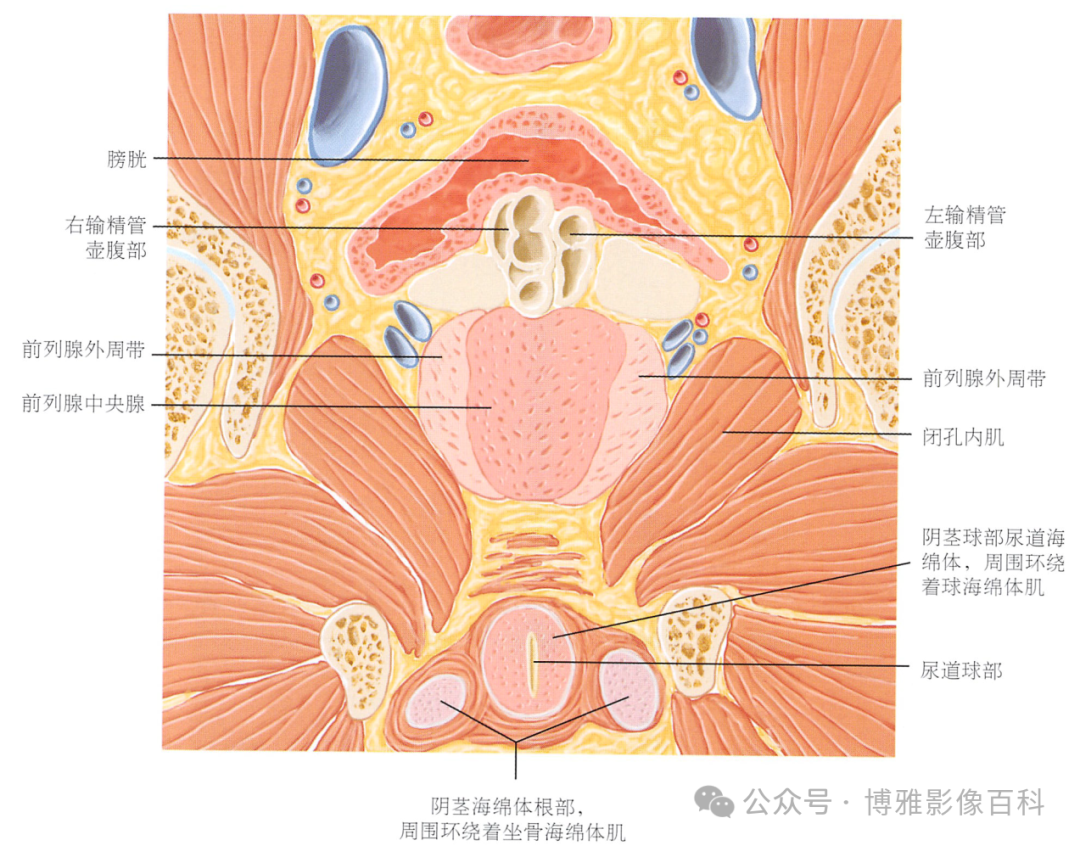

MR 解剖学

前列腺良性增生患者的轴向T2 图像,其他方面正常。外周带是一薄层均匀的高信号,边界清晰连续性的低信号包膜。移行带通常表现为不均匀中等信号,病灶被边界清楚的BPH良性前列腺增生结节所取代。精囊具有均匀T2高信号。未见淋巴结肿大。